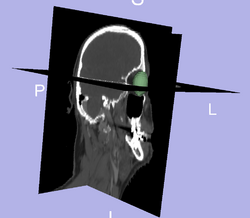

Proton therapy is used to deliver accurate doses of radiation to people undergoing cancer treatment. At the beginning of treatment, a personalized plan describing the amount of radiation and location to which it must be delivered is created for the patient. However, over the course of the treatment, which lasts weeks, a person's anatomy is likely to change. Adaptive radiotherapy aims to improve fractionated radiotherapy by re-optimizing the radiation treatment plan for each session. To update the plan, the CT images acquired during a treatment session are registered to the treatment plan and doses of radiation to be delivered are re-calculated accordingly. Registering a patient scan to a model (ex.Atlas) provides important prior information for a segmentation algorithm and in the other direction, having segmentation of a structure, can be used for better registration; hence, segmentation and registration must be done concurrently.

Initial experiments show that bony structures such as the mandible can be segmented accurately with a variational active contour. However, for soft tissue such as the brain stem, the intensity profile does not contain sufficient information for reasonably accurate segmentation. To deal with "soft boundaries" infinite dimensional active contours must be constrained by using shape priors and/or interactive user input. One way to constrain a segmentation is shown in our work in MTNS; there, known spatial relationships between structures is exploited. First, a structure we are confident in will be segmented. Using probabilistic PCA a metric used to describe how likely the structure whose segmentation we have obtained is; this metric is essentially a description of how confident we are in the correct segmentation. Then, the location of this structure will be used as prior information(it becomes a landmark) to segment a more difficult structure. Iteratively, the nth structure to be segmented will have n-1 priors do draw information from with a confidence metric for each prior. The likely location of the nth structure, calculated as described above, will serve as an input to constrain an active contours algorithm. Additionally, we have had excellent results when constraining structures of the eye to simple geometrical shapes such as ellipses and tubular to limit the number of free parameter. A sample segmentation of the eye ball is shown below.